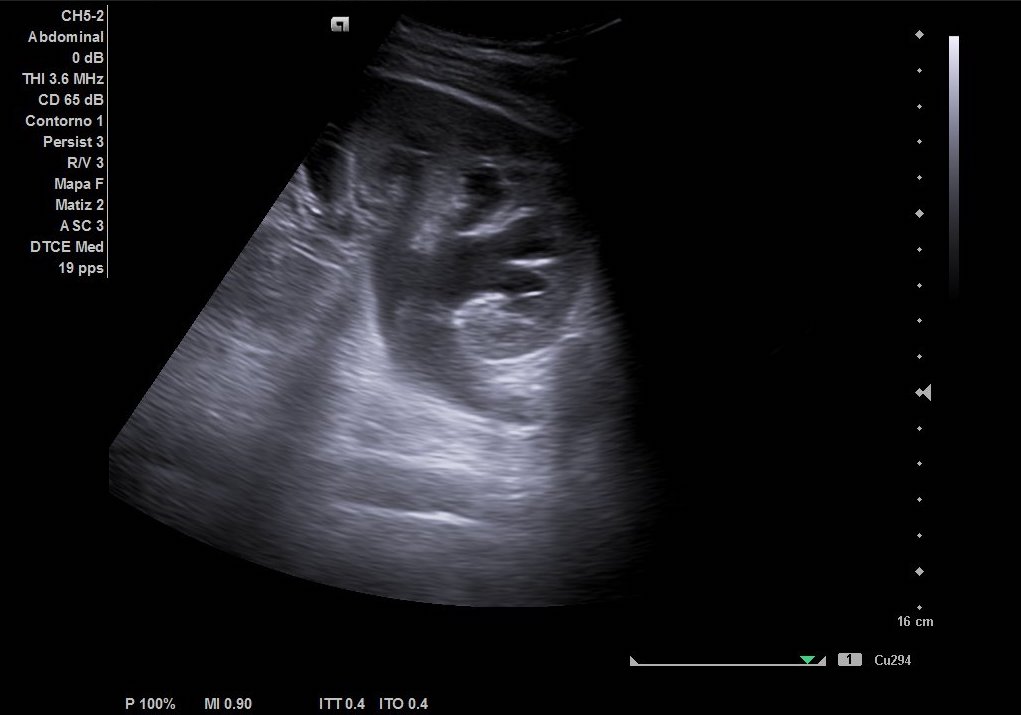

Hallazgos ecográficos

Como hallazgos, observamos dilatación del uréter proximal con hidronefrosis grado II-III. Sin visualización de imágenes compatible con litiasis. Riñón derecho de tamaño y ecoestructura normal sin dilatación de vía excretora. Vejiga vacía y ausencia de liquido libre.

Juicio clínico: Cólico renoutreteral izquierdo con hidronefrosis grado III.